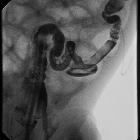

Fluoroscopy: contrast enema

Contrast enema may demonstrate a small caliber to the left colon with multiple filling defects within due to retained meconium. The rectum is usually normal in size, unlike Hirschsprung disease. The use of high osmolar ionic contrast media for enema in a neonate or infant is controversial due to the risks associated with fluid shift . The enema can be both diagnostic as well as therapeutic and is usually accompanied by the passage of meconium during or after the procedure.